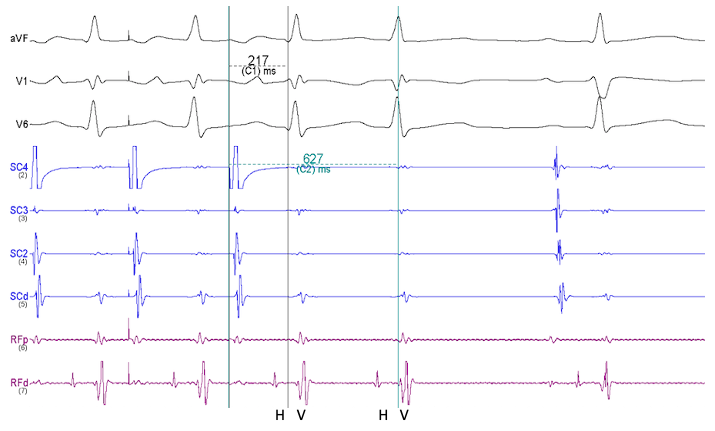

La taquicardia ventricular fascicular (TVF) es una forma rara de taquicardia ven...